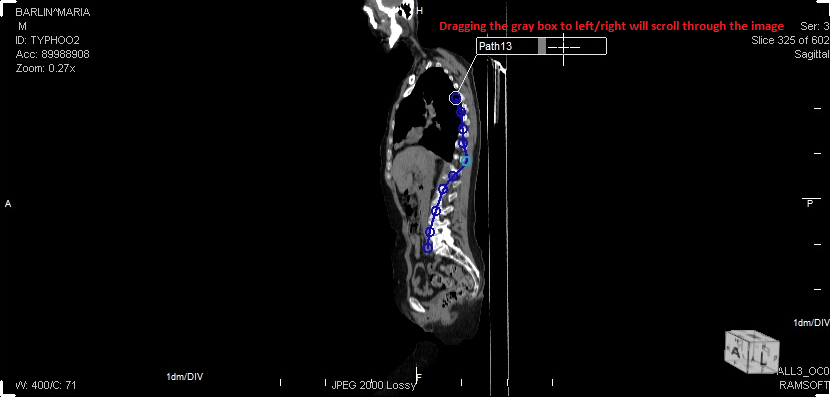

The user must create the straightened path.

The user must press Ctrl + Double-Click on the left mouse button at one specific point in the scale to mark it as the first point of reference.

The user can then press Ctrl + Double-Click on the left mouse button on another point in the scale to mark it as the second reference point.

The distance between the two points is displayed in blue (as shown in Step above).

If you wish to adjust the distance between the two reference points, you can do so by clicking and dragging one of the reference points on the scale.

To scroll through the images of a path, click on the gray square in the middle of the path label and drag it left-right. This dragging will allow you to scroll through the images of the path.